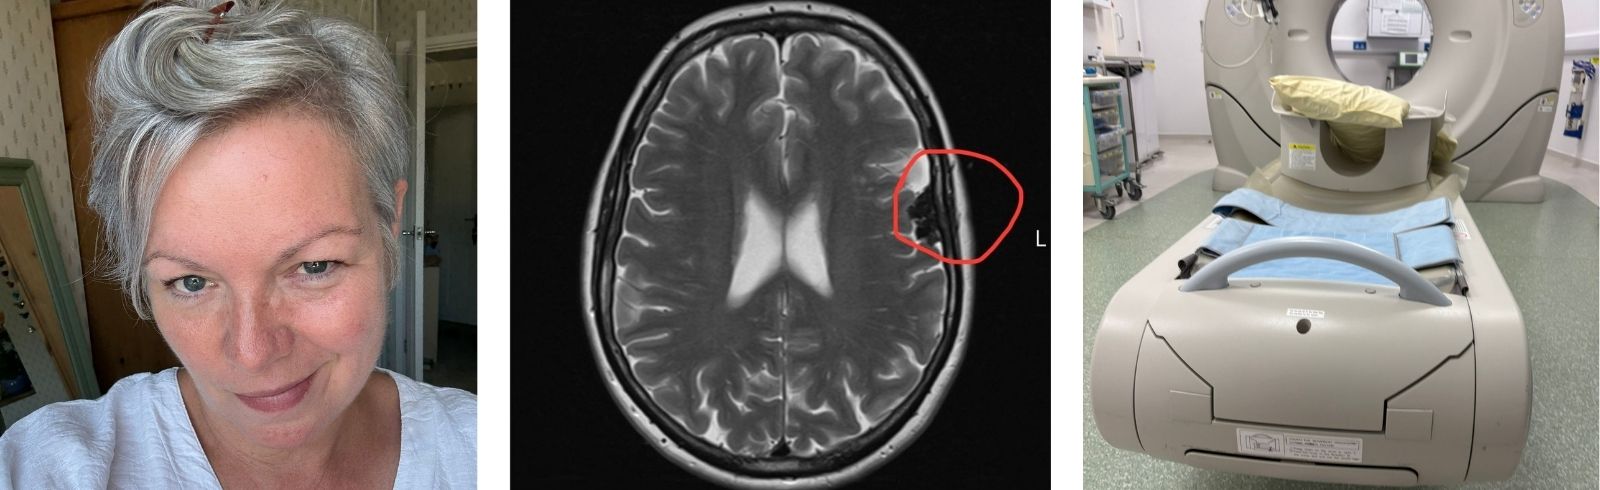

As the leading voice of the brain tumour community, we bring news from across the worlds of research, campaigning and fundraising. Read the latest brain tumour stories and news here.